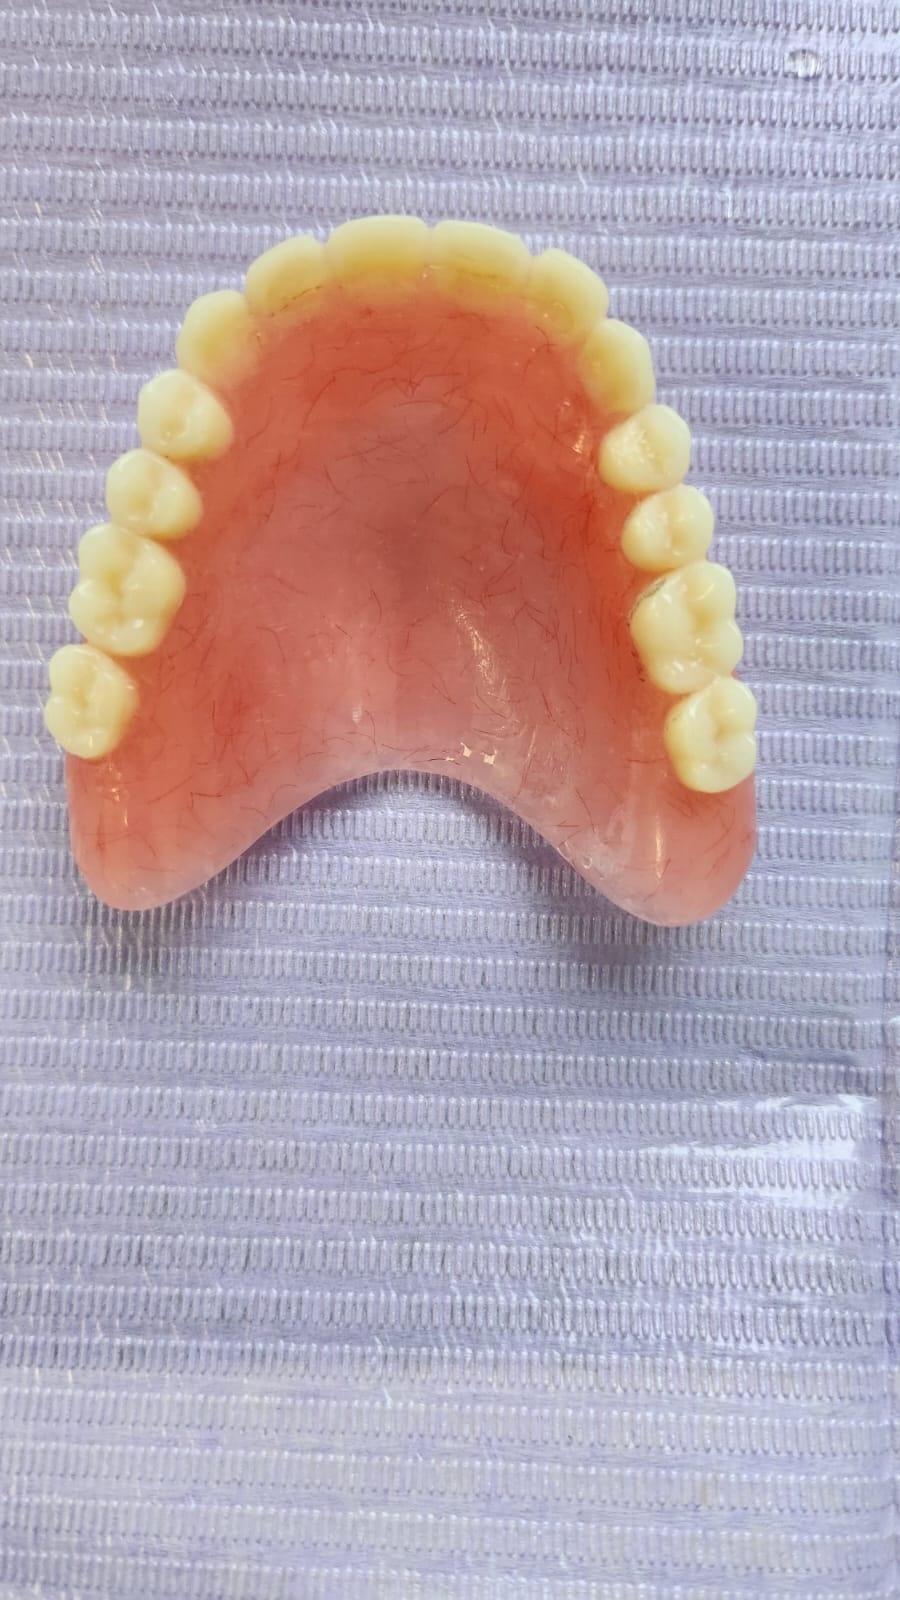

SUPRAPROTEZAREA PE IMPLANT